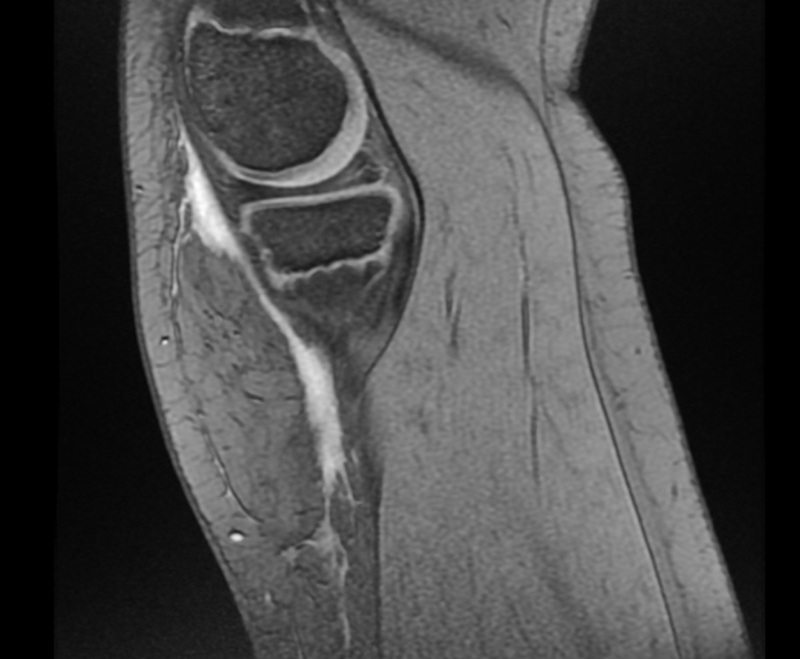

Una tu­mo­ra­ción con nom­bre pro­pio

Niño de 10 años que acude por dolor en la rodilla derecha desde hace mes y medio tras una caída desde la bicicleta, con persistencia del dolor y cojera intermitente. Presentó una erosión extensa con hematoma en esa rodilla.